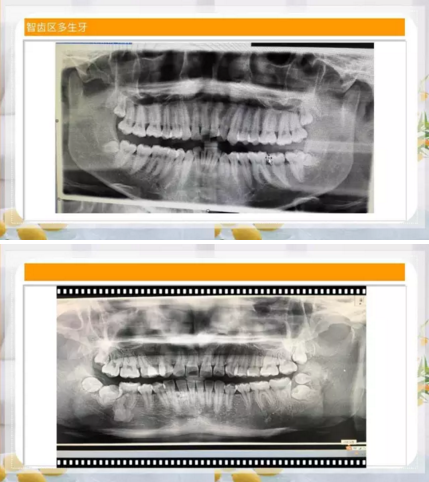

智齒區(qū)多生牙

9.png

10.png

11.png